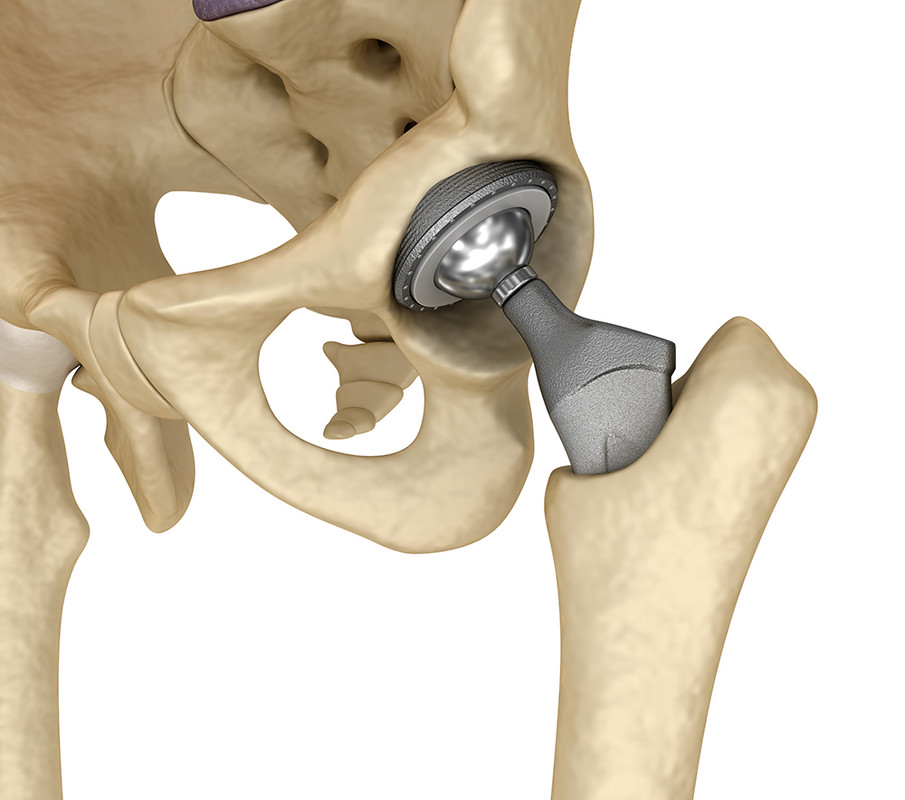

Хирург выполняет доступ к тазобедренному суставу, разрез кожи выполняется в верхней трети бедра. После того как тазобедренный сустав обнажен, хирурги вывихивают изношенную головку бедренной кости из вертлужной впадины. Затем производится резекция поврежденной головки и шейки бедренной кости специальной электрической пилой.

Далее с помощью специальных фрез обрабатывается вертлужная впадина. Во время обработки полностью удаляется изношенный хрящ и формируется полусфера, в которую будет имплантирован вертлужный компонент.

После формирования вертлужной впадины хирург заполняет впадину костным цементом и устанавливает подходящий по размеру вертлужный компонент. На этом этапе важна правильная пространственная ориентация вертлужного компонента под правильным углом. Это влияет на срок службы эндопротеза и вероятность развития осложнений в послеоперационном периоде.

После застывания цемента и фиксации вертлужного компонента, хирург приступает к бедренной кости. На данном этапе производится разработка костного канала бедренного канала специальными рашпилями до требуемого размера. Далее в подготовленный канал в бедренной кости помещается цемент и устанавливается бедренный компонент.

Подбирается головка требуемого размера и бедренный компонент вправляется в вертлужный. После хирург проверяет стабильность бедра и объем движений.

Как только хирург убедился, что все установлено должным образом, рана послойно ушивается. Устанавливаются дренажи на сутки. Пациент отправляется в специальную палату в послеоперационном отделении. С первых суток начинается реабилитация пациента.